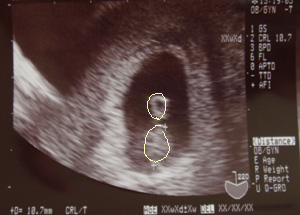

子宮内に受精卵の着床が確認されたときのエコー写真。(8週目)

↑あたりの袋が受精卵です

妊娠してからいろいろ身体に変化があって~3ヶ月半頃までいろいろ戸惑いました。